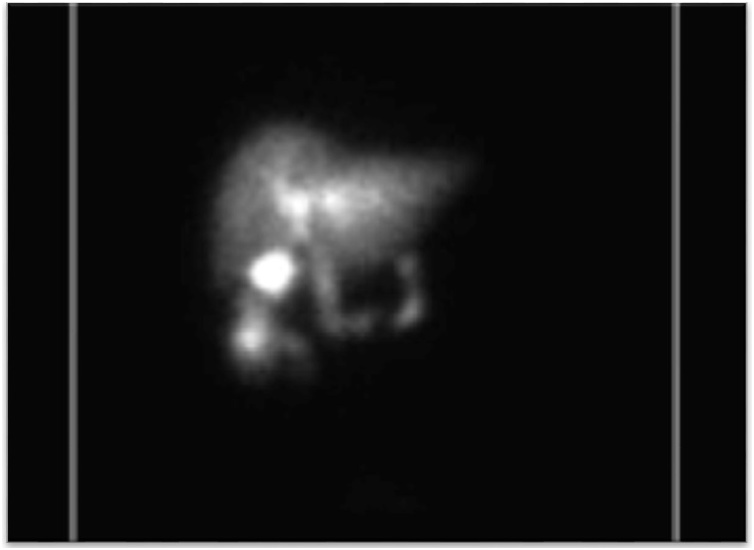

Ultrasound (US) imaging demonstrated a thickened gallbladder wall up to 5 mm with an apparent shadowing suggesting a gallstone as well as some pericholecystic fluid. Due to extensive ring-down artifact on US, computed tomography (CT) imaging was obtained and elicited concern for cholecystocolonic fistula (Fig. 1); with pneumobilia, inflammation and enhancement in the area of the gallbladder fossa and common bile duct (CBD), as well as thickening extending into the adjacent colon at the hepatic flexure. The patient underwent two weeks of antibiotic therapy. Preoperative Hepatobiliary scintigraphy was compatible with a cholecystocolonic fistula to the hepatic flexure of the colon (Fig. 2). However, preoperative colonoscopy was unable to locate the fistula tract.